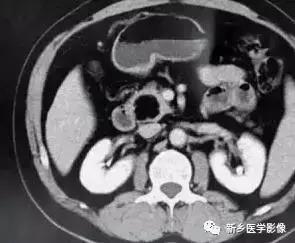

四、胰腺转移瘤

胰腺转移瘤在临床上较为少见, 1000 例恶性肿瘤尸检中,仅3 %有胰腺转移。原发肿瘤可为肺癌、乳腺癌、肾细胞癌、卵巢癌、结肠癌、黑色素瘤等。胰腺不是肿瘤转移的常见部位。胰腺转移瘤的影像学表现与原发肿瘤有一定关系, 可表现为乏血供或富血供胰腺肿块, 有时E RCP 可示主胰管内充盈缺损。转移

瘤的影像学表现少有特异性,且发病率很低,故诊断常依靠原发肿瘤的确诊以及胰腺病变的细胞学检查。